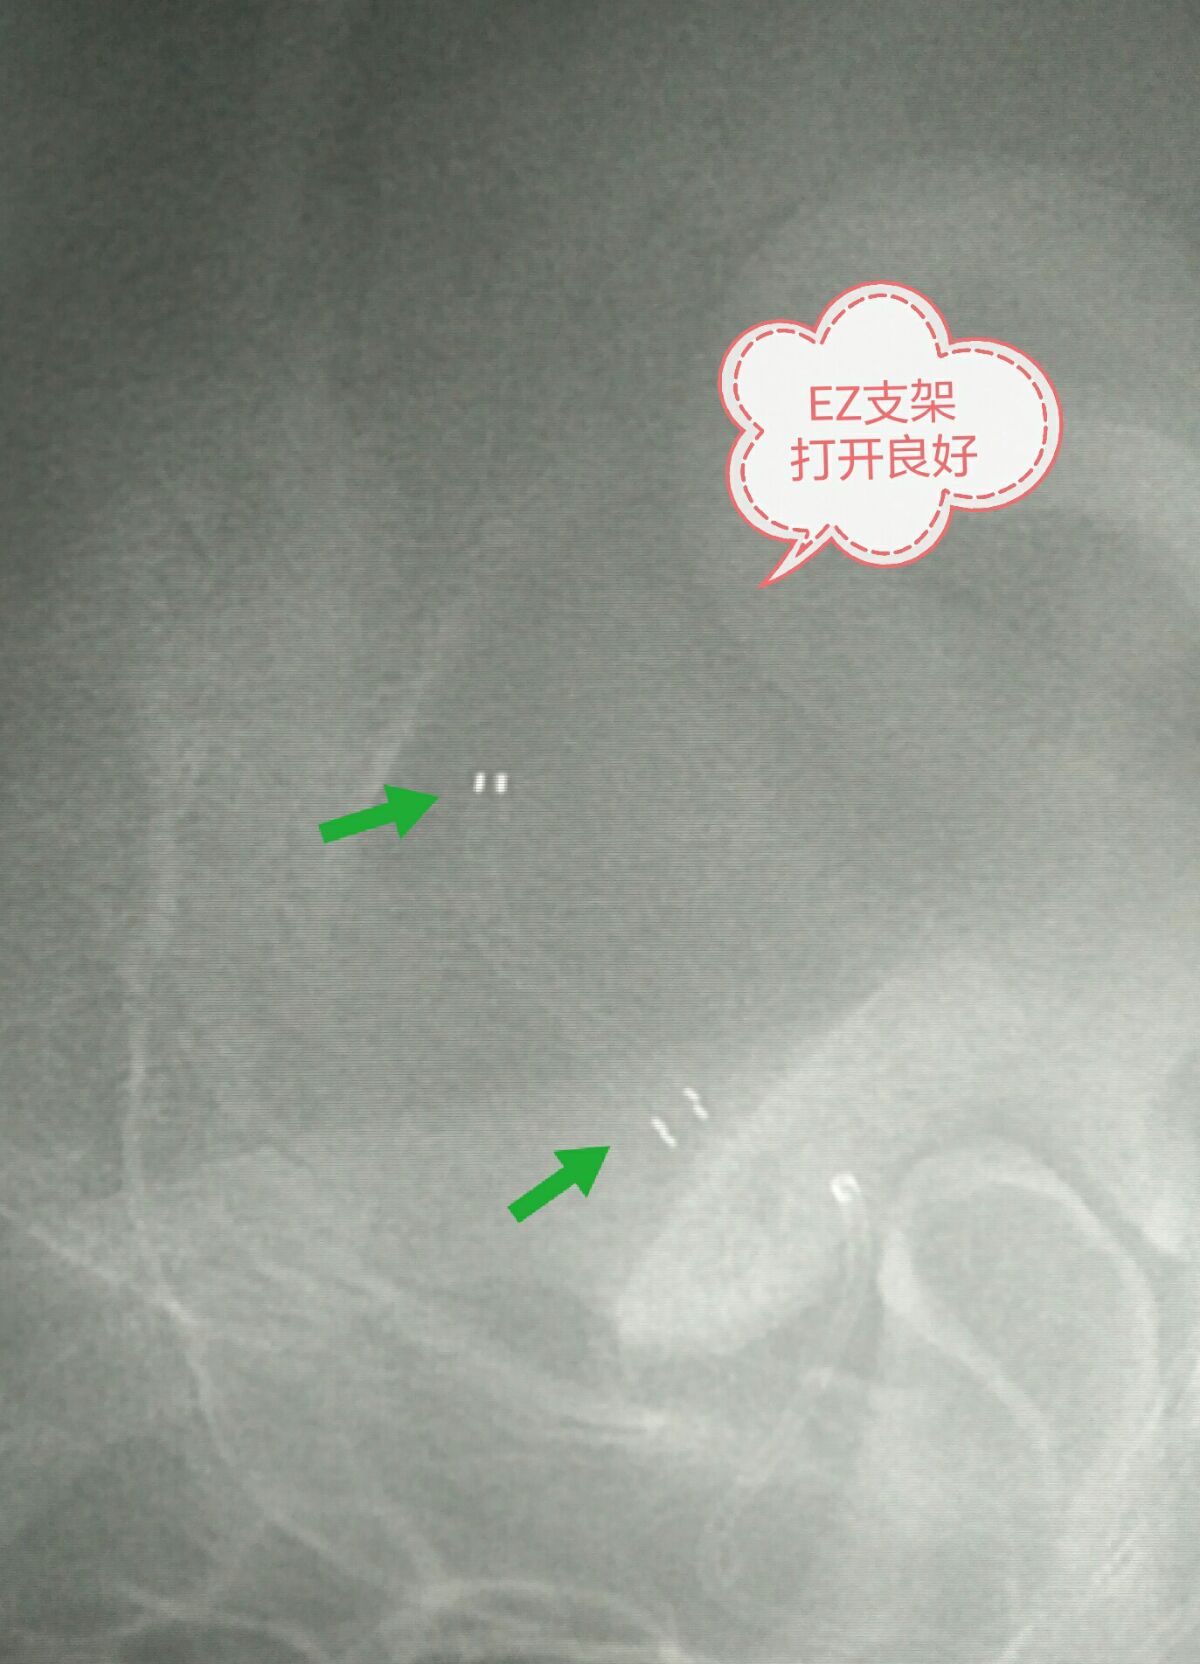

非剪影像显示支架展开充分

反转像显示支架展开充分